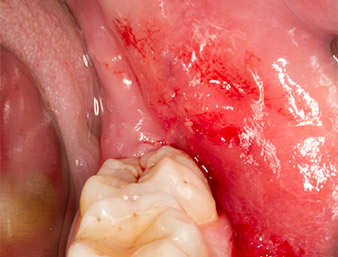

After block and local anaesthesia, the operating site was opened up and the soft tissue exposed for buccal retromolar access (Fig. 3).

sulcular incision

Fig. 3: The sulcular incision begins in mid-tooth 36 (LL6), with distal extension on the ascending ramus.

The tissue above the root remnant was not completely ossified and consisted for the most part of granulation tissue modified by inflammation (Fig.4).

Granulation tissue

Fig. 4: Two Langenbeck retractors and a raspatorium expose the operating area. Granulation tissue of the incompletely healed first osteotomy can be seen.